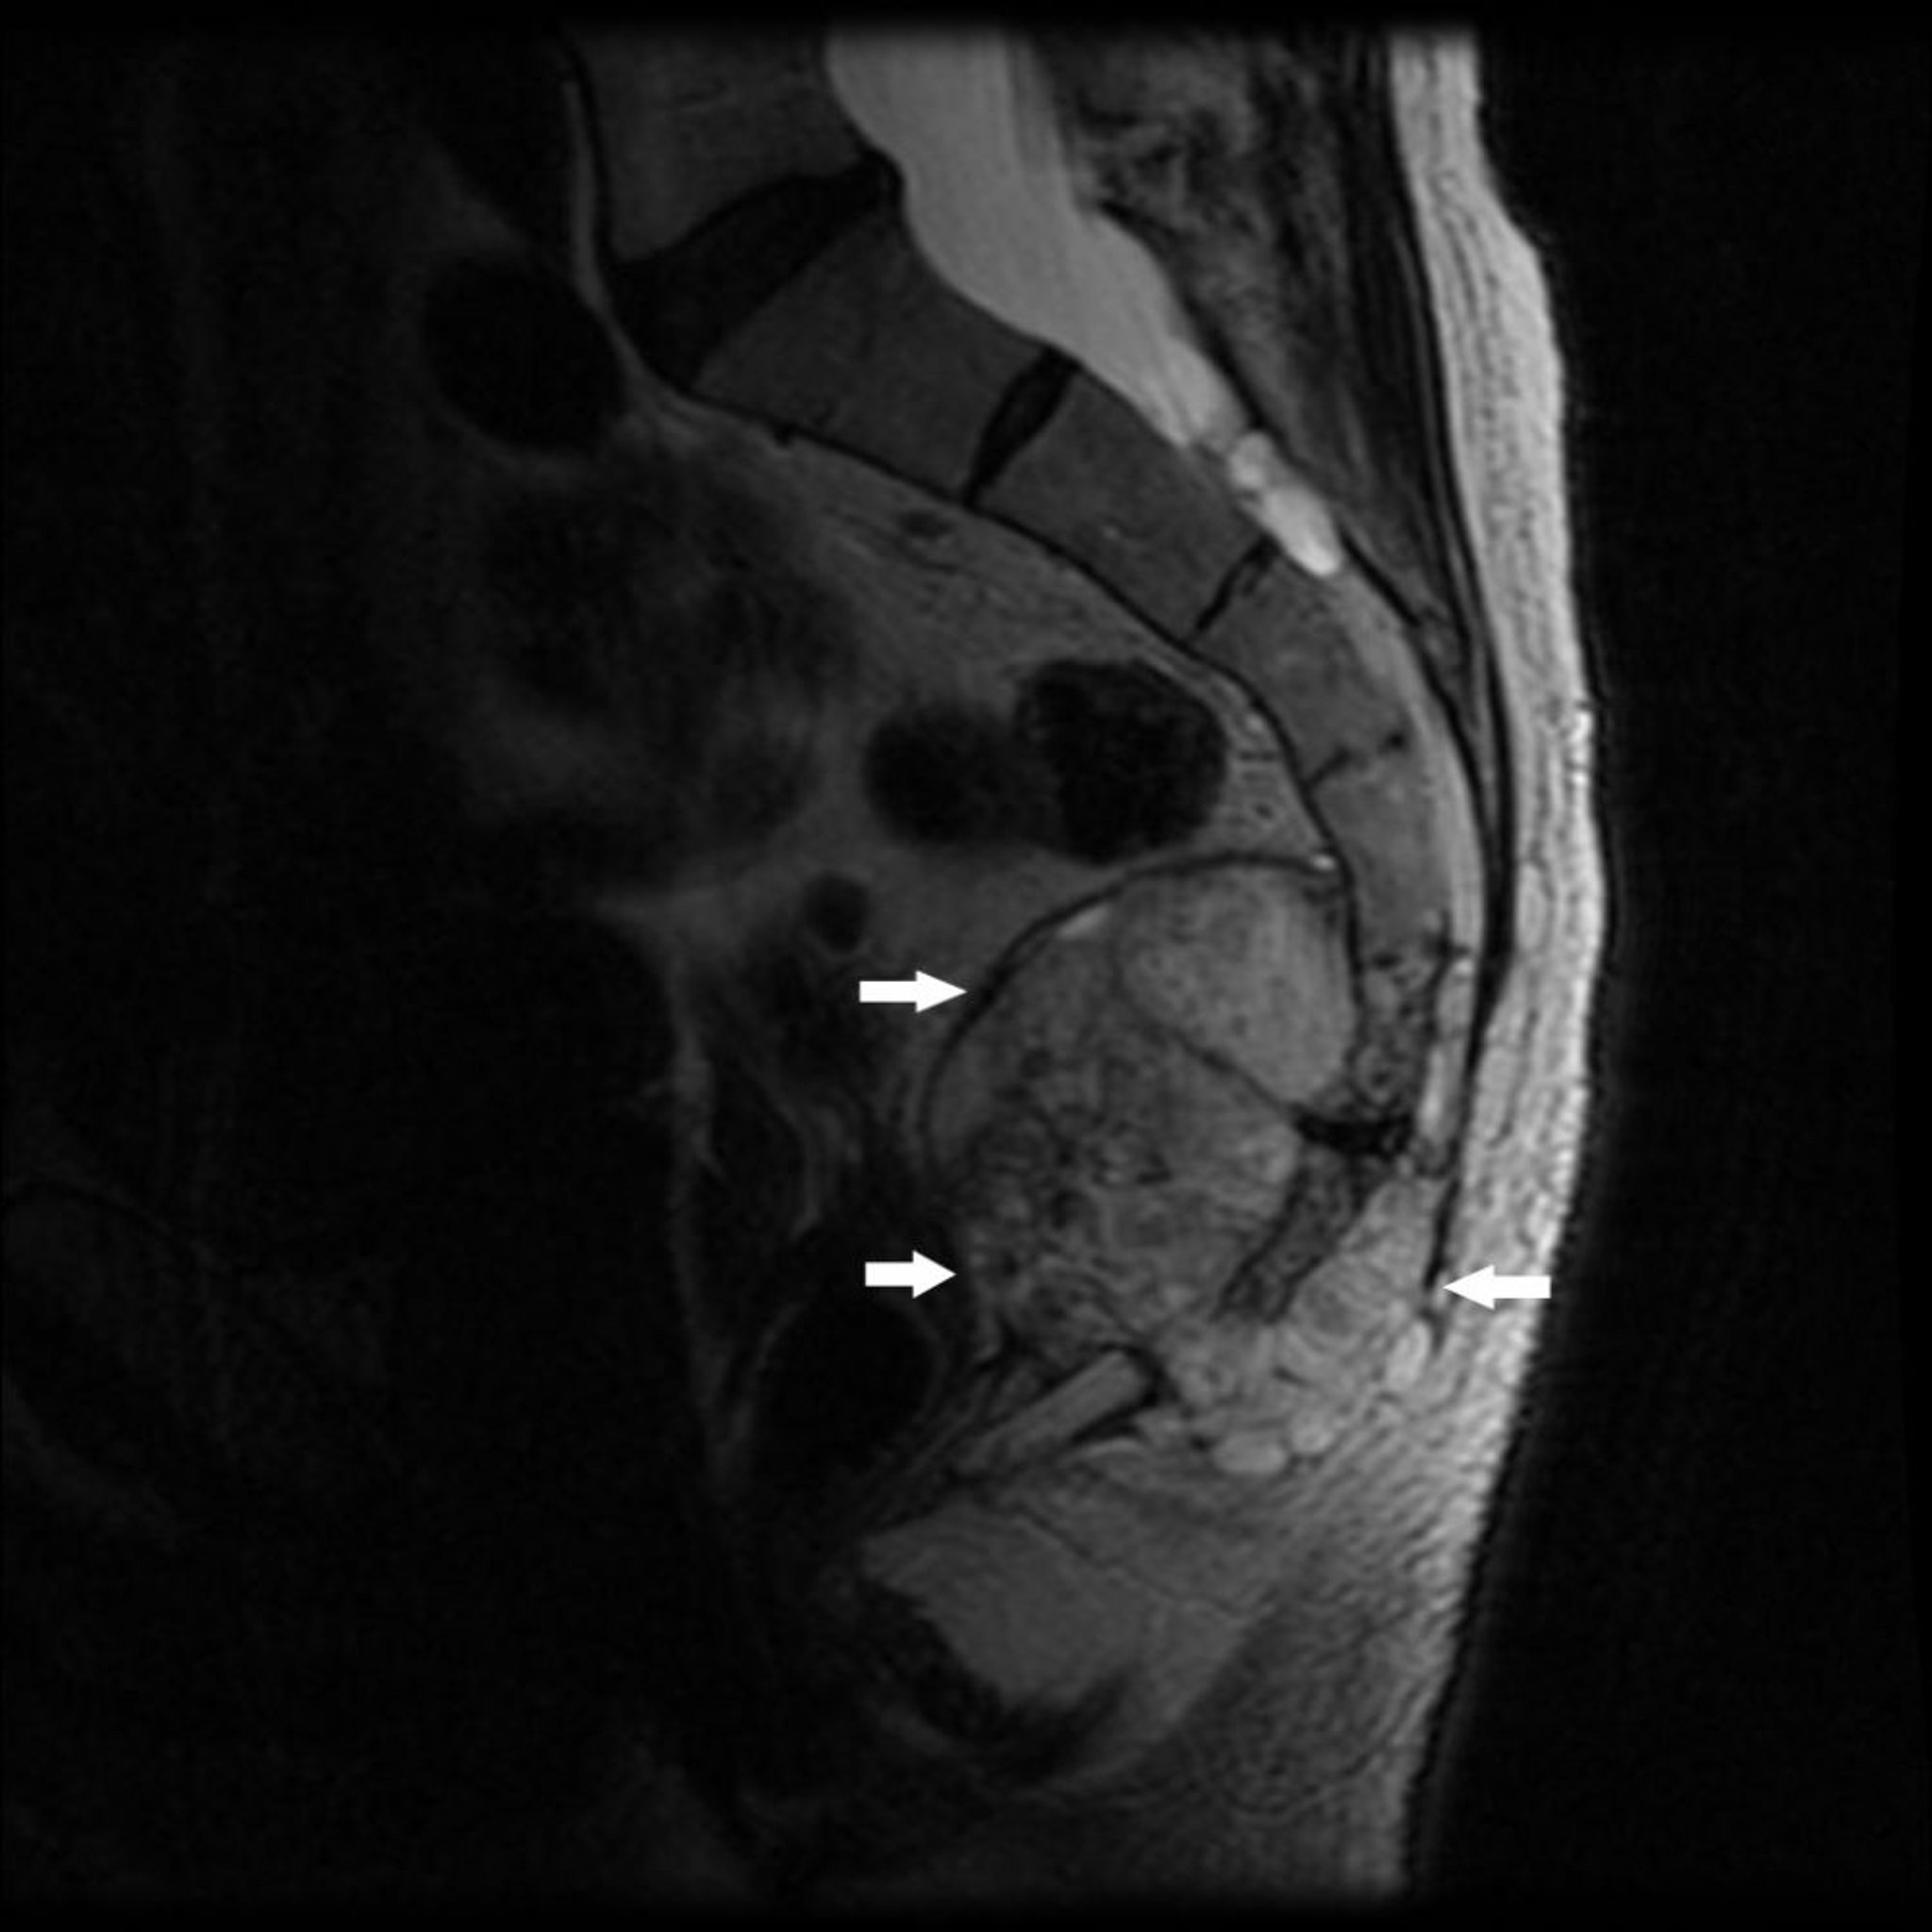

Questa risonanza magnetica mostra un tumore all'estremità caudale del sacro (S4) e del coccige con distruzione ossea e massa di tessuto molle (frecce), tipica di un cordoma.

Image courtesy of Michael J. Joyce, MD, and Hakan Ilaslan, MD.